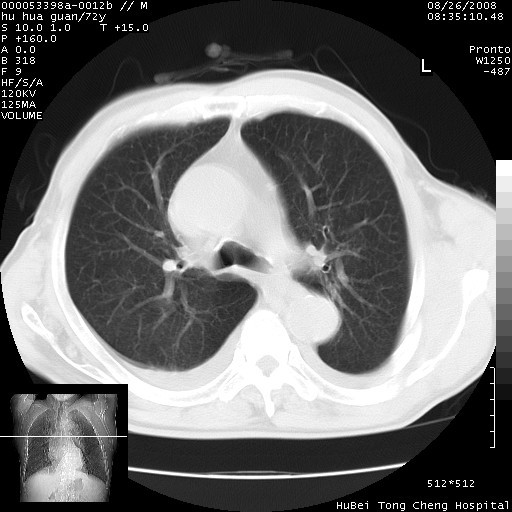

可以明确的说。肯定不是主动脉夹层破裂出血!考虑为淋巴瘤或间叶组织来源的恶性肿瘤可能性大。右肺小结节建议薄层观察,如能发现恶性征象,那椎前改变就考虑为转移所致。至于双侧少量胸水乃静脉血回流受阻所致。

降主动脉前移位,后纵隔占位

后纵隔占位,降主动脉前移位;双侧胸腔积液;应排外食管病变侵犯血管可能;

建议排除结核引起的冷脓肿。